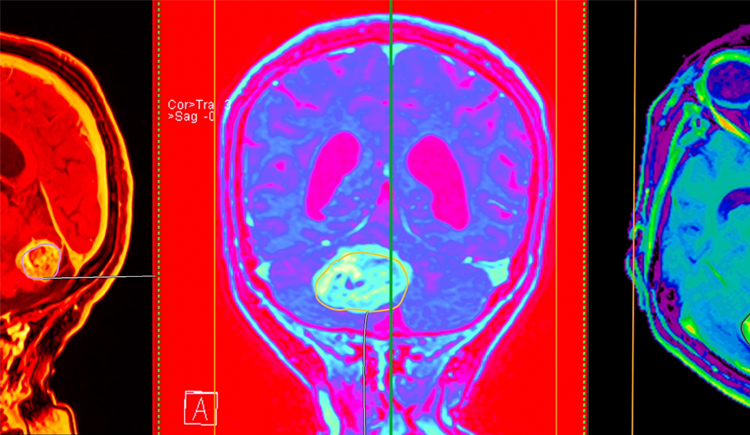

A Harvard Medical School-led research team has developed an AI tool that can reliably tell apart two look-alike cancers found in the brain but with different origins, behaviors, and treatments. The tool, called PICTURE (Pathology Image Characterizati... [2675 chars].. reed more